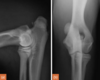

3.5m Yorkie

lateral humeral condylar fracture

lateral humeral condylar fracture - see its caudal displacement, superimposed over the cranial ulna.